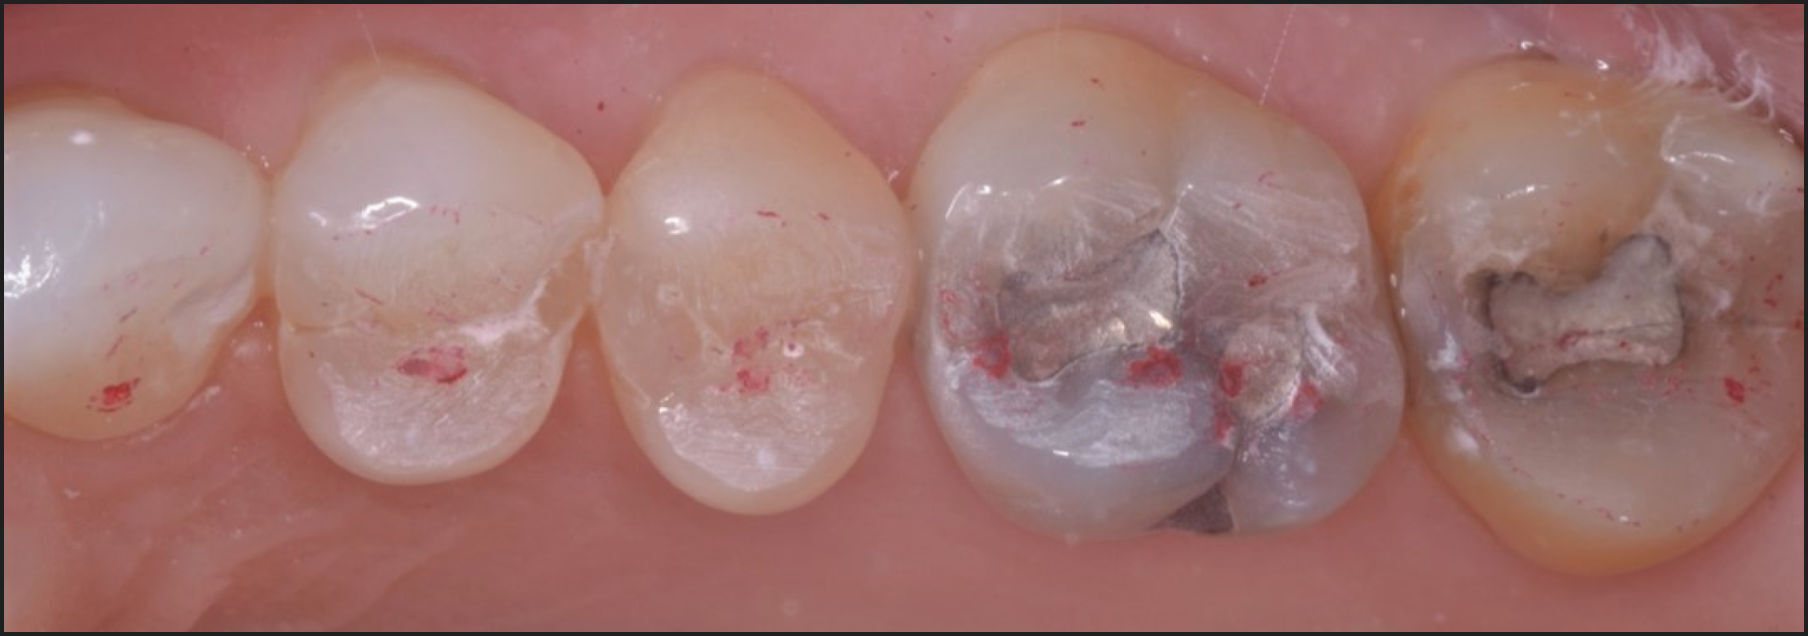

The subjects’ teeth were air dried. The patients were then asked to close into their Maximum Intercuspal Position (MIP) with articulating paper (Bausch, Arti-Fol® Red, 8μ, Germany) interposed between their teeth, and then to commence a right mandibular excursion out to edges of their canine teeth, then slide back into MIP, and then make a left mandibular excursion out to the edges of the left side canine teeth, and back into MIP (Figures 3A - 3C).

The pre-treatment T-Scan/BioEMG recordings (Figures 2A and 2B) guided the clinician to the areas to adjust, where prolonged excursive frictional contacts were located on inclined planes and on outer aspects of the buccal cusps (Figures 3D and 4A). These excursive contacts were then eliminated on all involved surfaces using pear-shaped finishing burs (Mani Dia-Burs, Japan ISO no-237/021) bilaterally, leaving the central fossa, cusp tip, and the marginal ridge contact points intact (Figure 4B).

All lace-like linear contacts had been removed

The remaining pattern of habitual closure contacts were located solely on cusp tips, fossae, and marginal ridges (Figure 4B).